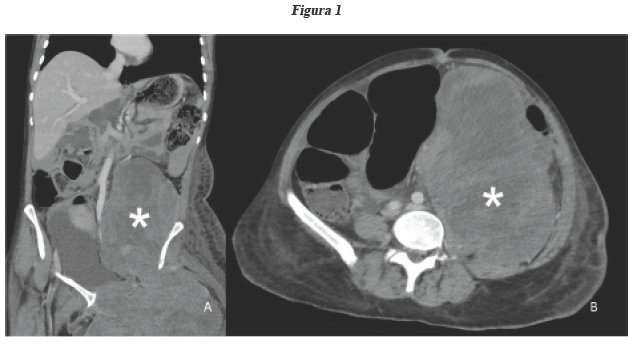

Se trata de una paciente mujer de 45 años procedente de Perú, portadora de Sarcoma Sinovial (SS) monofásico de muslo izquierdo, sin seguimiento después de mala respuesta a la quimioradioterapia. Ingresó 6 meses después, por un cuadro compatible con obstrucción intestinal. Al examen físico, se encontró un abdomen distendido y doloroso a la palpación, a nivel de tercio superior de muslo izquierdo una extensa tumoración de bordes irregulares, de 30 cm que ocupa la totalidad del compartimiento anterior. La tomografía de abdomen mostró una extensa tumoración que compromete el músculo ilíaco izquierdo y condiciona obstrucción intestinal, asociado a edema del miembro inferior izquierdo (ver Fig. 1). La paciente negó el tratamiento quirúrgico.